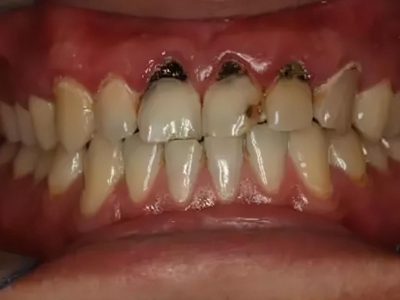

酸蚀症牙齿缺损严重有黑斑图

酸蚀症严重时会使牙齿出现大面积缺损,有三颗下牙损毁严重,露出不整齐的牙骨质边缘,几乎仅余留牙根。缺损处有黑斑,局部呈黄褐色,需积极就医进行牙齿修复。

酸蚀症牙齿缺损发黑图

酸蚀症患者上门牙大部分缺失,累及周围牙体,牙釉质和牙本质出现大面积深度腐蚀破坏,牙颈部出现坑状缺损,露出黄褐色、黑色的缺损面牙体。